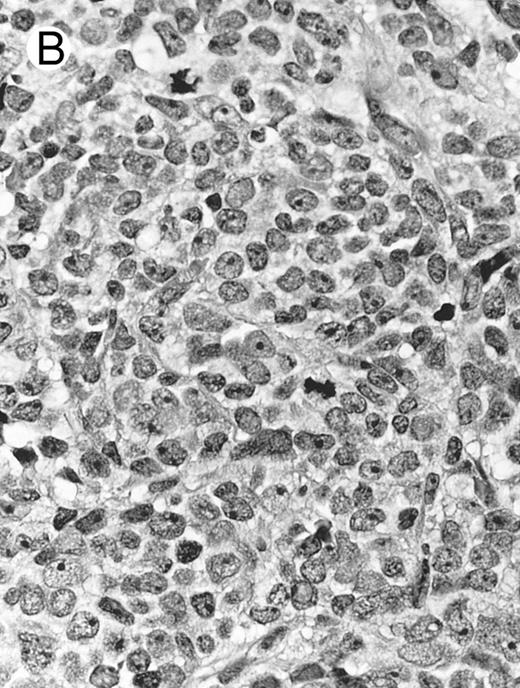

Lymph node biopsy of aggressive NK cell leukemia/lymphoma (case no. 37). There is a fairly monotonous, diffuse infiltrate of medium-sized cells with round nuclei. The neoplastic cells in this case resemble plasmacytoid monocytes.

There were very few to numerous granular lymphocytes in the peripheral blood. Some of the granular lymphocytes were indistinguishable from normal large granular lymphocytes, with round nuclei, dense chromatin, and pale cytoplasm with fine azurophilic granules (Fig 5A). Some granular lymphocytes had larger nuclei with more open chromatin and distinct nucleoli (Fig 5B); occasional nuclei could show indentations. The azurophilic granules were sometimes large and coarse. There were also circulating normoblasts and immature myeloid cells. Marrow involvement ranged from subtle to extensive. In histologic sections, irrespective of site, there was a monotonous infiltrate of medium-sized cells with round nuclei and fairly condensed chromatin (Fig 6). Karyorrhexis was prominent. The infiltrate was diffuse, interstitial, or angiocentric.